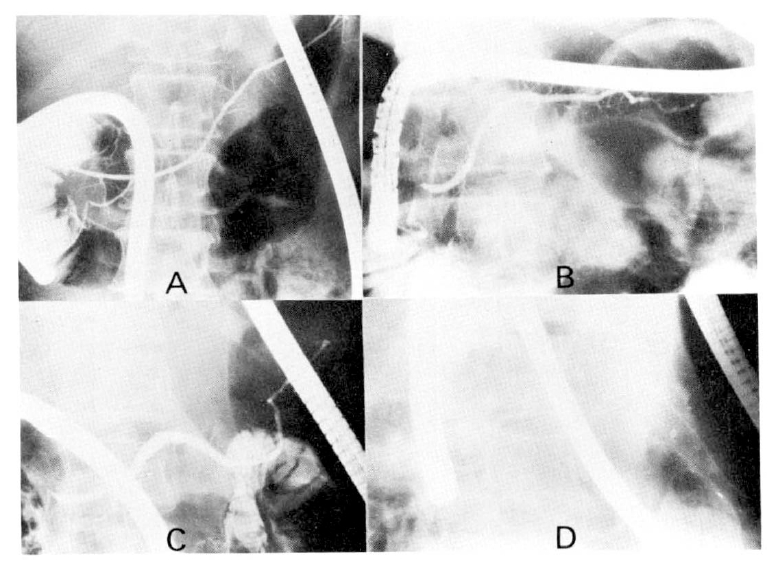

Pancreatic ductal extensions are various in that they can be classified as ascending, horizontal, sigmoid and descending types (Fig. 1). Of 286 cases studied, the ascending type was most prominent at 51.7%, sigmoid type 25.2%, horizontal type 24.2% and descending type 0.7% (Table 3.)

Fig 1

Types of course of the main pancreatic duct on endoscopic pancreatogram. A, the ascending type. The duodenum is demonstrated simultaneously with a pancreatogram. B, the horizontal type showing the fine pancreatic duct. C, the sigmoid type. D, the descending type.